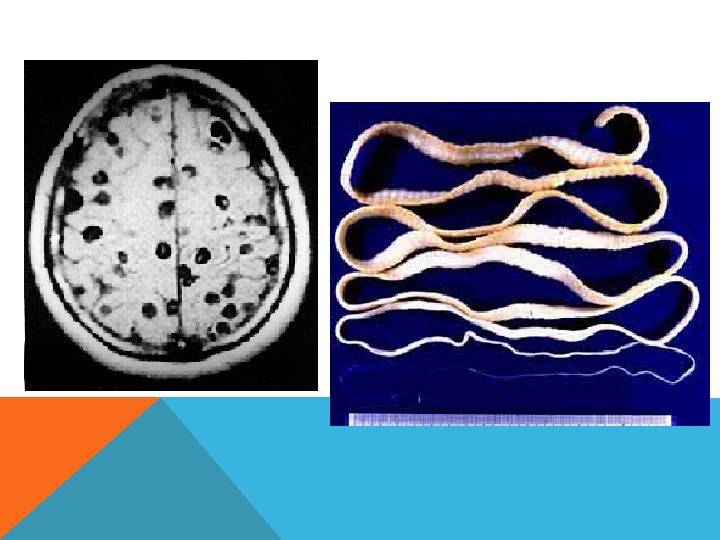

ЦИСТИЦЕРКОЗ Цистицеркоз (cysticercosis) — гельминтоз из группы цестодозов, характеризующийся в зависимости от локализации паразита поражением кожи, подкожной клетчатки, мышц, головного и спинного мозга, глаз, внутренних органов, костей. Возбудитель — личинки свиного цепня (Tanenia solium).

Эхинококкоз - редкое паразитарное заболевание нервной системы, возникающее в результате воздействия на организм личиночной формы ленточного гельминта Echinococcus granulosus. Заражение происходит при попадании в желудочно-кишечный тракт человека яиц эхинококка - небольшого ленточного червя (Taenia echinococcus), живущего в кишечнике собак и волков.